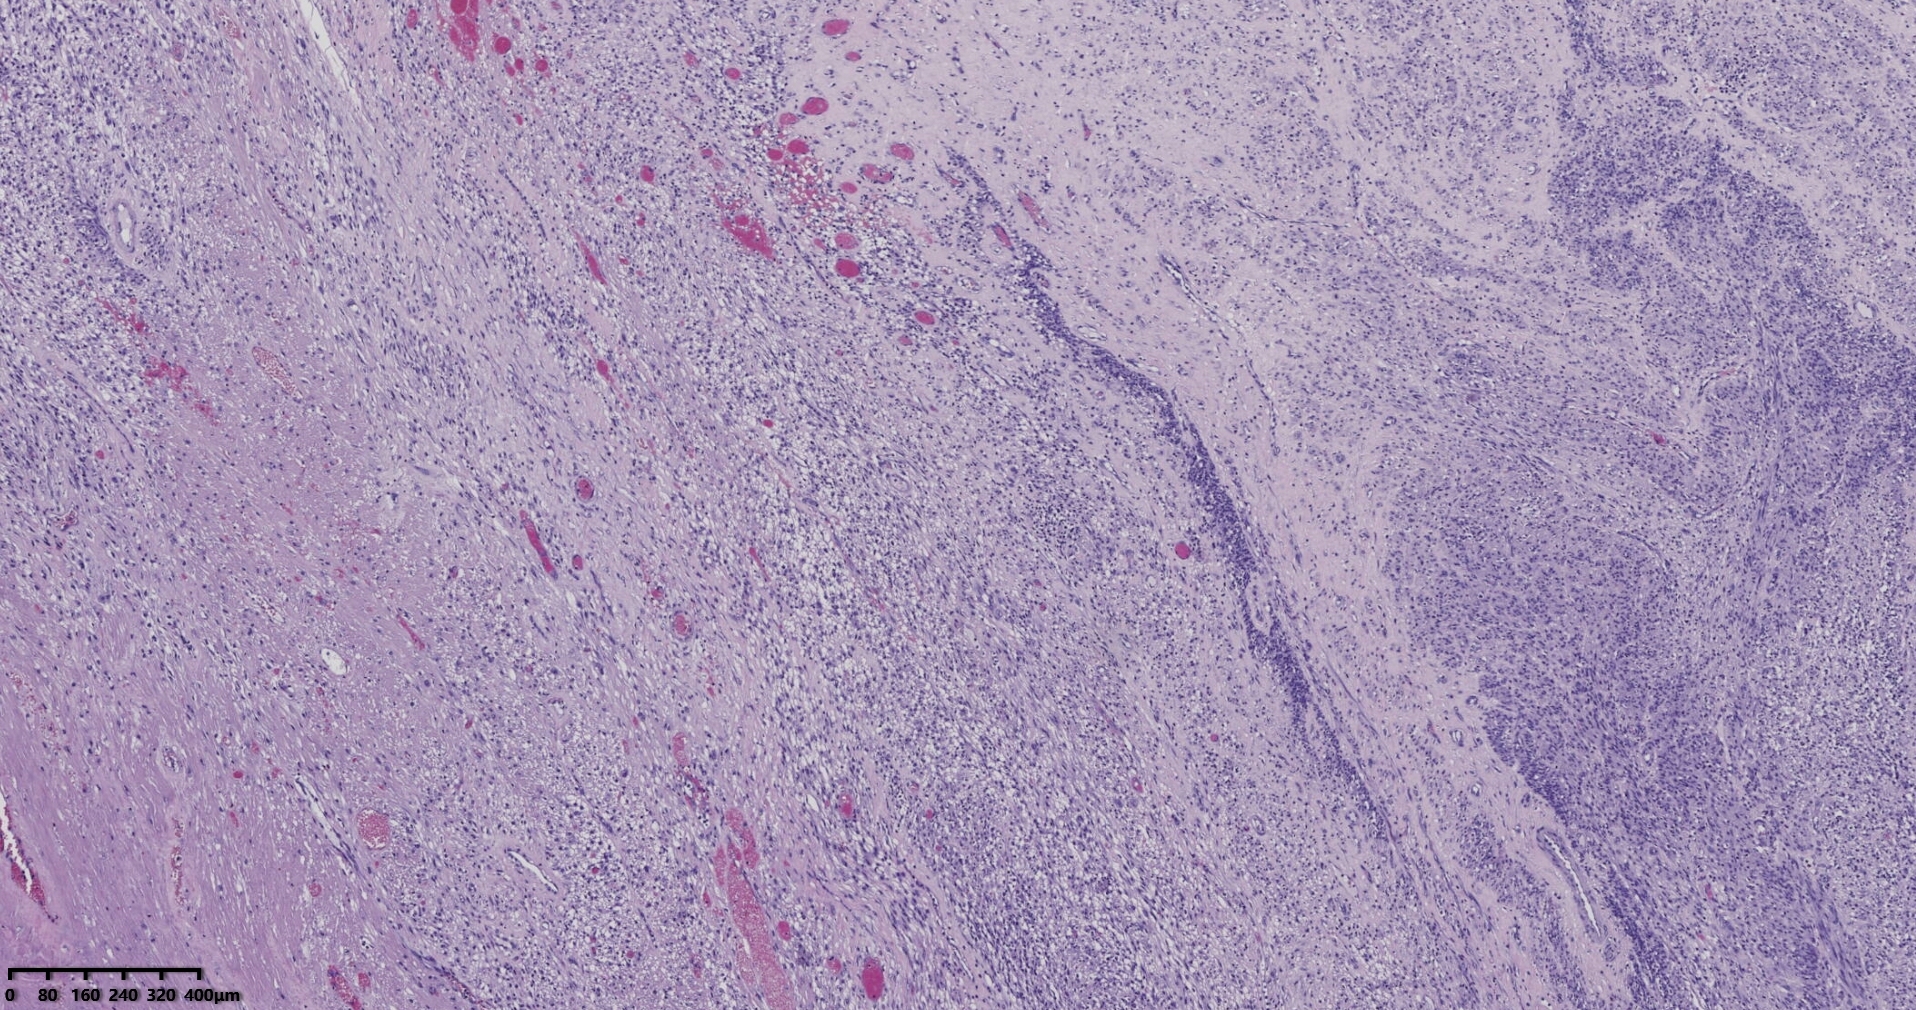

送检灰白肿物十余个,直径多在2-3厘米,切面均为灰白、实性,质地韧,其中一个大肿物,直径约7厘米,切片灰白灰红,质地韧当时取材时印象还是平滑肌瘤,伴变性,不考虑肉瘤,因为形态规整,质地韧,不脆,切面灰白,不是灰黄。

镜下所见小肿物无特殊,大肿物瘤细胞密集,中心区有变性、坏死,瘤细胞核有异型性。大肿物补充取材,发现,部分区域切面灰黄,这个区域,瘤细胞更密集,异型性更显著。肿物边缘有薄层正常平滑肌组织被覆,靠近边缘瘤细胞最密集,局部瘤组织内小血管较丰富。

会诊:考虑平滑肌肉瘤。

北医三院会诊:子宫平滑肌瘤伴红色变性可能性大,建议加做免疫组化及NGS检测进一步明确诊断。